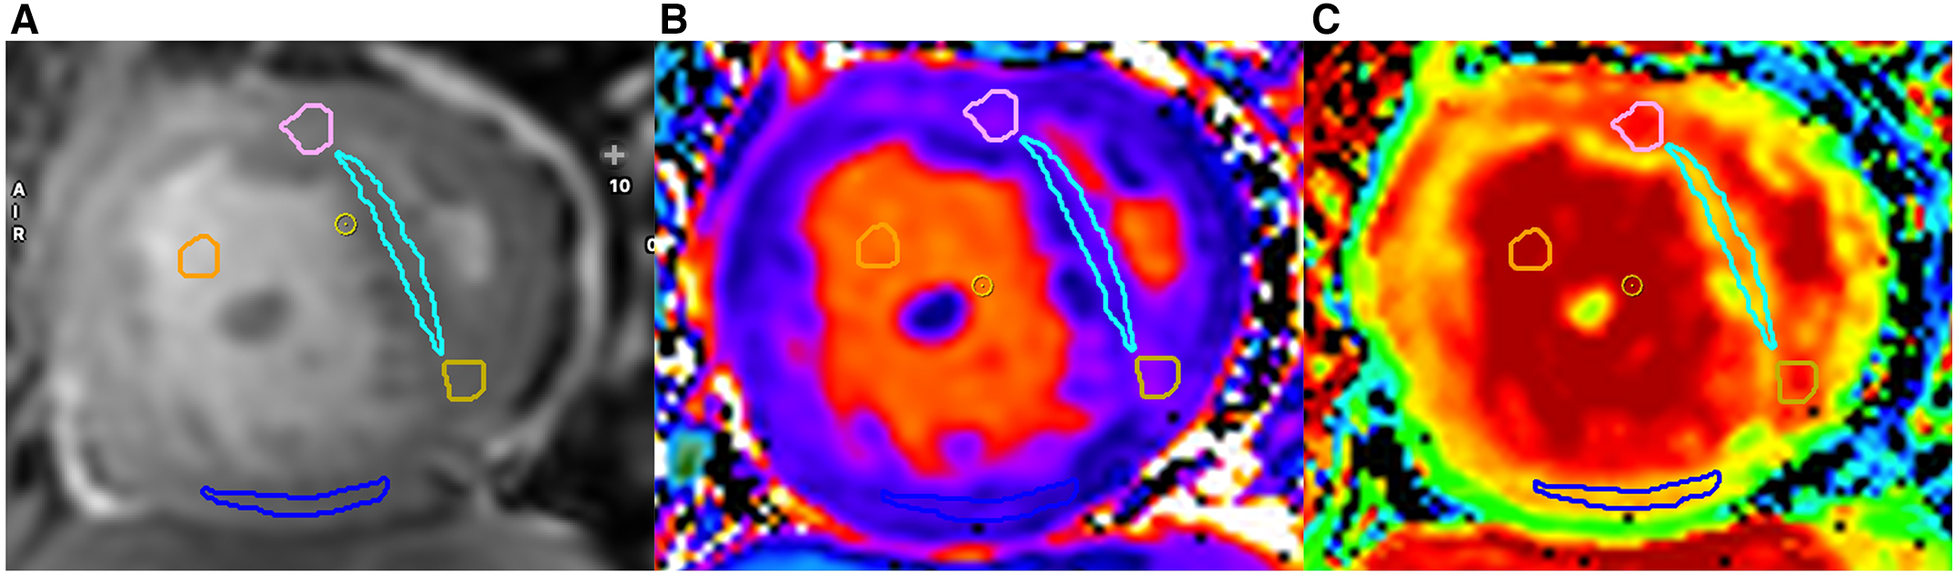

Native T1 measurement was obtained by manually drawing regions of interest (ROIs) in four locations on the midventricular short-axis plane including the anterior RVIP, IVS, posterior RVIP, and inferior RV free wall (Figure 2). ROIs were drawn with a minimum size of 12 pixels in each location and blinded to LGE findings. ROIs were carefully drawn on dense myocardial tissue without including non-myocardial structures such as trabeculae, epicardial fat, and blood pool. Native T1 values from each ROI location were recorded and averaged from four ROI locations.

Figure 2

Examples of ROI locations obtained on cine images (A), native T1 (B), and ECV map (C) are shown. Each ROI from every region is distinguished by a different color: anterior right ventricular insertion point (RVIP) (pink), interventricular septum (light blue), posterior RVIP (yellow), inferior wall of the RV (blue), and blood pool (orange).

Post-contrast T1 RV measurements were obtained on post-contrast maps using ROIs at the same locations as native T1 measurements. ECV calculation involved acquiring pre- and post-contrast myocardial T1 values at the same locations. Blood pool T1 values before and after contrast administration, along with hematocrit values, were also used for ECV calculation according to the formula and calculated automatically by the CVI42 program.